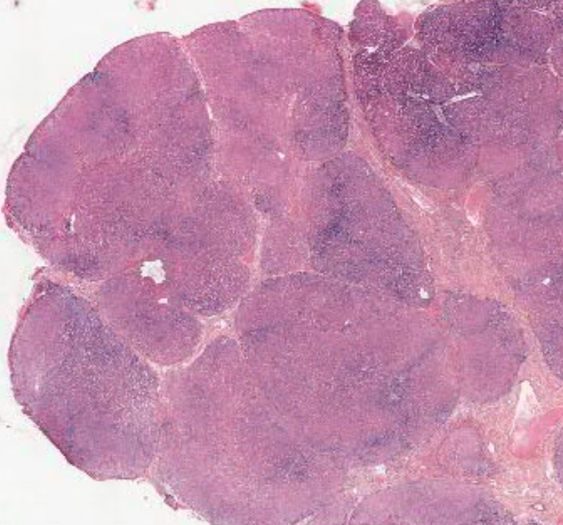

细胞和组织的适应与损伤

肾小球硬化症(AP044,HE 染色 & 番红染色)